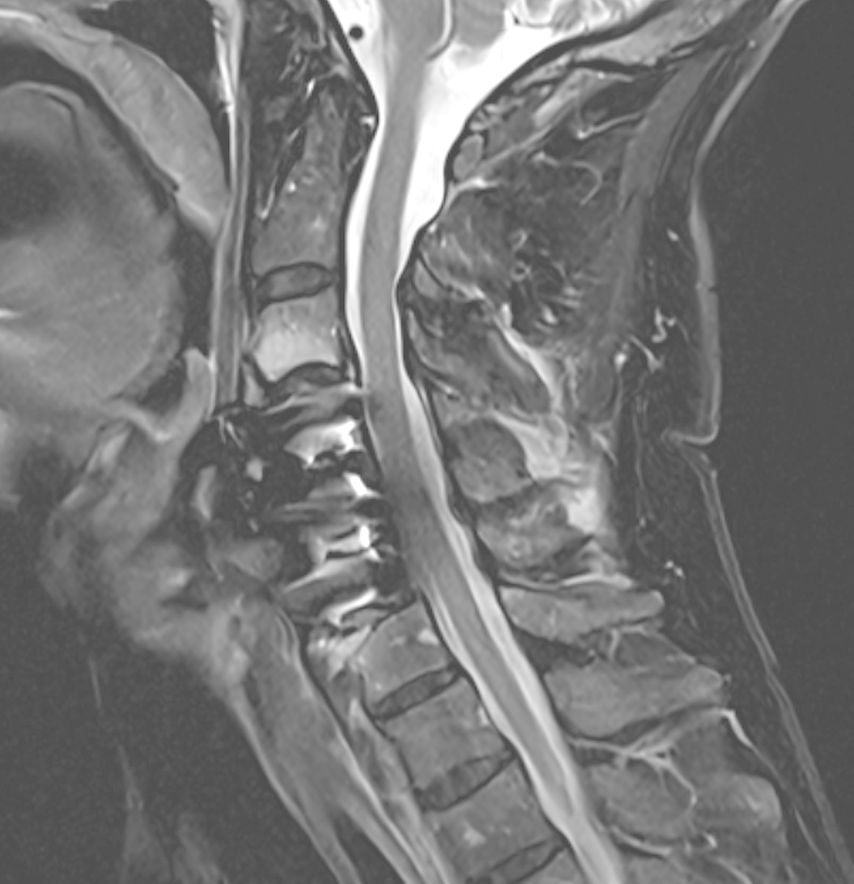

Beispiel für die Implantation zervikaler Pedikelschrauben. In diesem Fall kam es bei einem 61-jährigen Patienten 10 Jahre nach anteriorer zervikaler Diskektomie und Fusion (ACDF) C4/5 und ventraler Verplattung C4–6 zu einer Ankylosierung auch von C6/7. Nach Sturz kam es zu einer Fraktur bei C6/7 mit begleitender Bogenfraktur und auch Beteiligung der dorsalen Ligamenta (Abb. 1 und 2). Klinisch bestanden ausgeprägte Nackenschmerzen und kein neurologisches Defizit. Es wurde die Indikation der dorsalen Verschraubung von C4 auf Th1 gestellt. Intraoperativ wurde routinemäßig zusätzlich eine kleine Referenzschraube in einer Lamina – entfernt von der Dornfortsatz-Referenzklemme für die Navigation – gesetzt. Mit dieser konnte intraoperativ die Genauigkeit der Navigation exakt überprüft werden (Abb. 4 und 5). Mittels navigierter High-Speed-Fräse wurden die Schraubenkanäle vorgebohrt (Abb. 6), im Anschluss wurde der Bohrkanal ausgetastet und die Schrauben wurden implantiert. Abbildung 7 zeigt eine Röntgenkontrolle 3 Monate postoperativ.

Die Navigation stellt nicht nur beim Einbringen von Implantaten eine Hilfe dar, sondern kann auch in anatomisch herausfordernden Situationen rein zur Verbesserung der Orientierung zu Hilfe genommen werden. Mögliche Anwendungsfelder stellen hier beispielsweise die untere HWS oder der zervikothorakale Übergang dar, welche im konventionellen Röntgen teilweise schwer darstellbar sind. Abbildung 16 zeigt den MR-Befund einer 32-jährigen Patientin, die auswärtig zur ACDF C6/7 indiziert wurde, wobei der Eingriff dort aber aufgrund der Unmöglichkeit, die HWS unter Durchleuchtung entsprechend einzustellen, nicht erfolgte. Abbildung 17 zeigt das intraoperative Röntgen mit bereits kräftigem Schulterzug, in dem aber nur mehr das Segment C4/5 sicher beurteilt werden kann. In diesem Fall erfolgte mittels O-Arm der Eingriff navigiert. Ein anderes Beispiel ist die Anwendung zur Orientierung bei Osteotomien, wo die Navigation an unserer Klinik ebenfalls standardmäßig angewendet wird. Abbildung 18 zeigt einen intraoperativen Screenshot im Rahmen der Navigationsanwendung bei einer thorakalen Corporektomie (Th12) von dorsal im Rahmen einer Tumorresektion. Auch bei verkalkten Bandscheibenvorfällen, wie in Abbildung 19 dargestellt, kann die Navigation zur besseren intraoperativen Orientierung herangezogen werden. Ein weiteres Beispiel der vielfältigen Anwendungsmöglichkeiten der Navigation zeigt Abbildung 20. In diesem Fall wurde im Rahmen einer C1/2-Verschraubung nach Harms das Gelenk C1/2 beidseits navigiert zur besseren Fusion angefrischt.